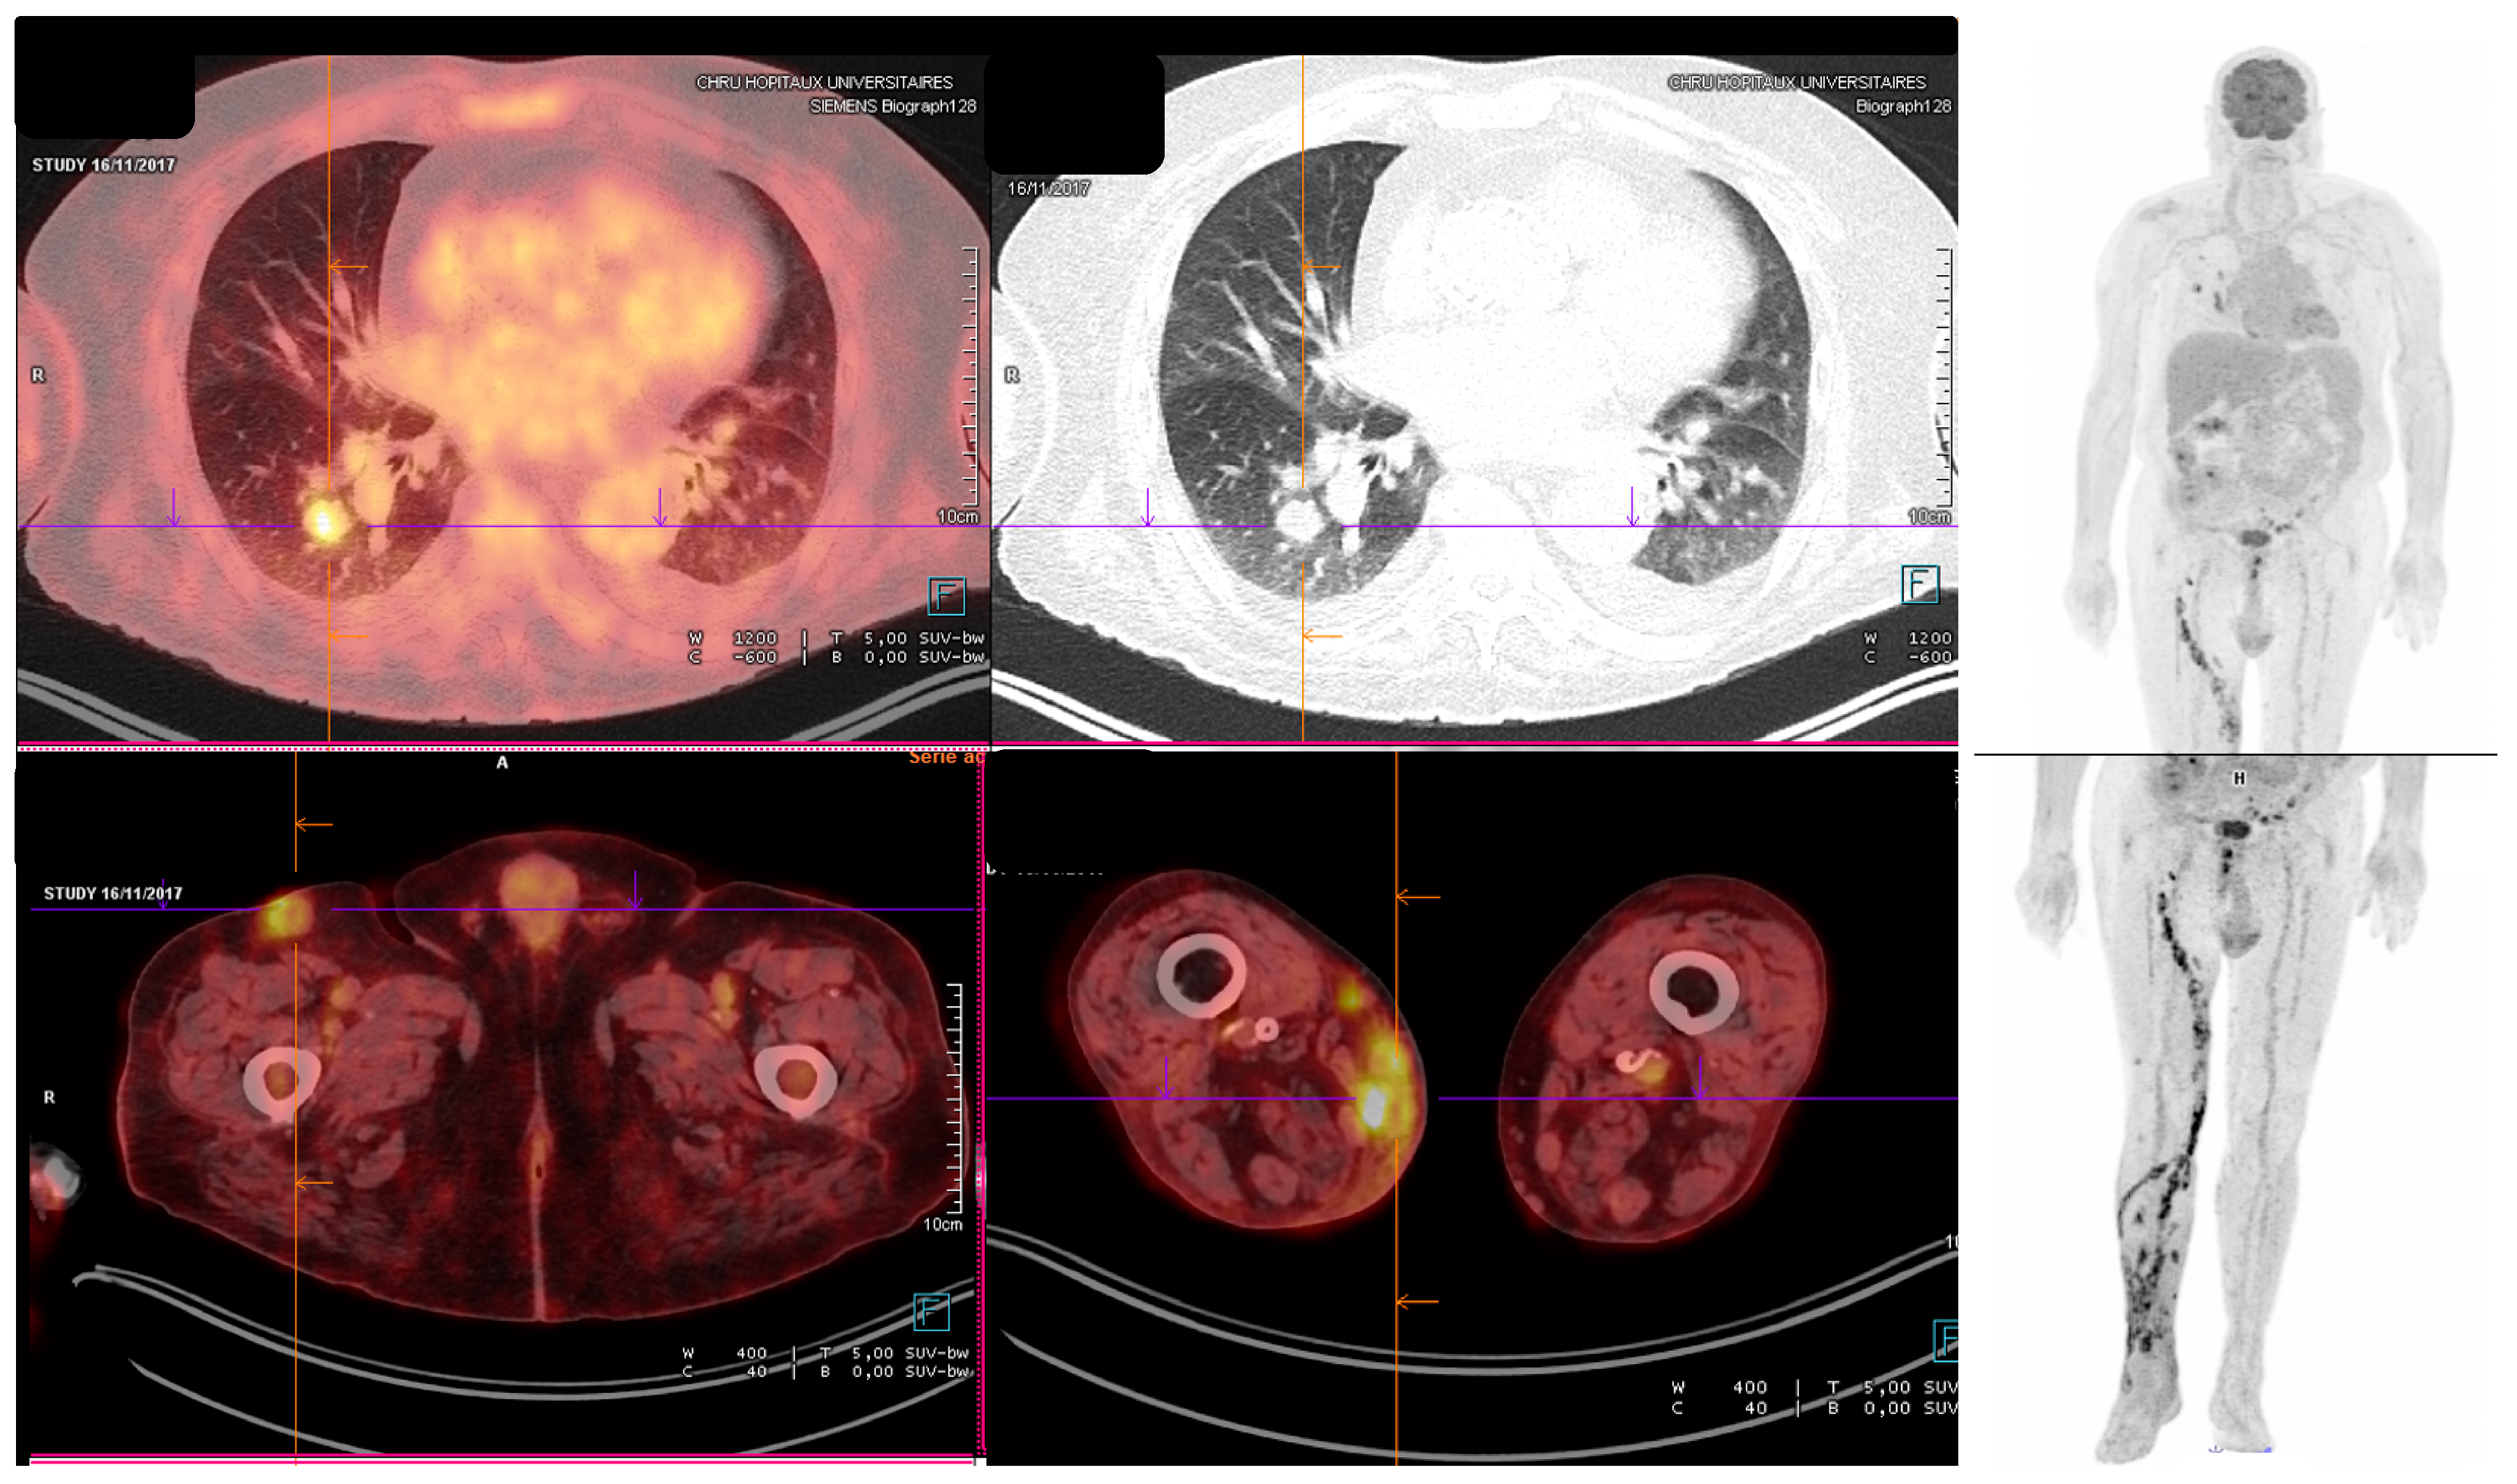

| Pulmonary infection without further extension | 39 | 42.4 | |

| Disseminated infection with pulmonary involvement | 17 | 18.5 | |